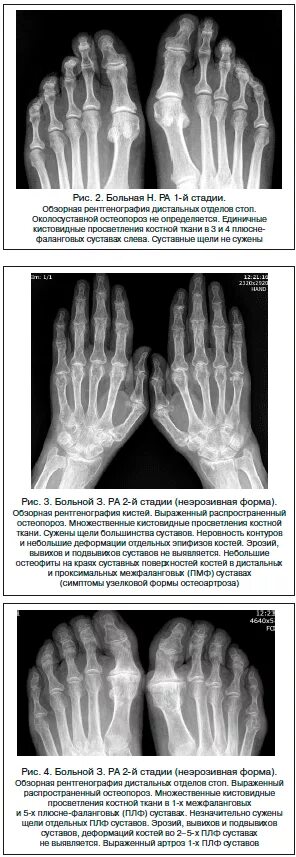

Артроз лучезапястного сустава 2 степени